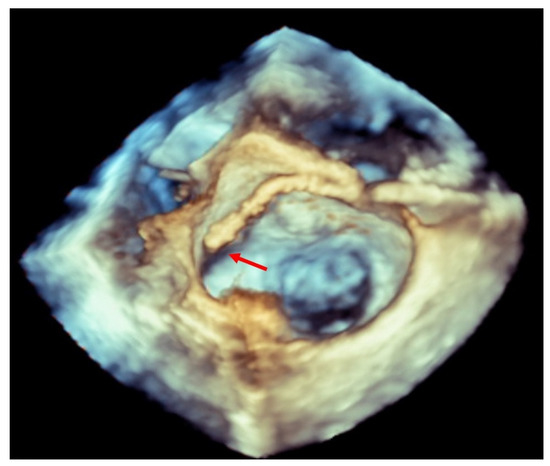

Transesophageal echocardiographically guided transseptal puncture aiming to achieve a posterior and superior position is the main key to avoiding potential complications in this procedure [6]. The use of 3D-TEE guiding has decreased the incidence of this complication, as well as the possibility of eroding the walls of the left atrium and neighboring structures with catheters and devices [2,7] (Figure 1).

Figure 1.

Three-dimensional transesophageal echocardiogram showing a clip inside the left atrium touching the lateral wall (red arrow).